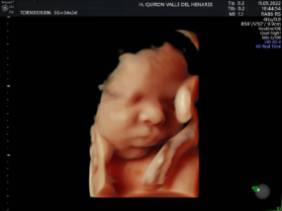

El Hospital Quirónsalud Valle del Henares incorpora un nuevo ecógrafo con tecnología 5 D

El Hospital Quirónsalud Valle del Henares ofrece la posibilidad de realizar ecografías gestacionales 5D. Este tipo de exploración permite obtener una imagen muy realista del bebé y se puede realizar en cualquier etapa de la gestación -aunque lo recomendado es realizarla entre las semanas 28 y 32 de gestación, ya que técnicamente es el mejor momento y es mucho más probable obtener imágenes de buena calidad-.

Al final de la prueba, se entrega a la familia un informe de la ecografía y un soporte digital que contiene las imágenes y los vídeos realizados. Las ecografías 4D y 5D son también llamadas emocionales por la explosión de sensaciones que genera cuando la madre ve por primera vez la imagen del bebé que espera.

"Realizar esta ecografía con nuestro equipo de diagnóstico prenatal tiene un valor añadido -señala la Dra. Rocío Vellido Cotelo, Jefa Asociada de Ginecología y Obstetricia del Hospital Quirónsalud Valle del Henares, dado que quien realiza la prueba es un especialista en la materia, siempre se completa la exploración con un examen morfológico y de perfil biofísico fetal, que permita valorar el estado de bienestar del bebé más allá de la captura de videos y fotografías".